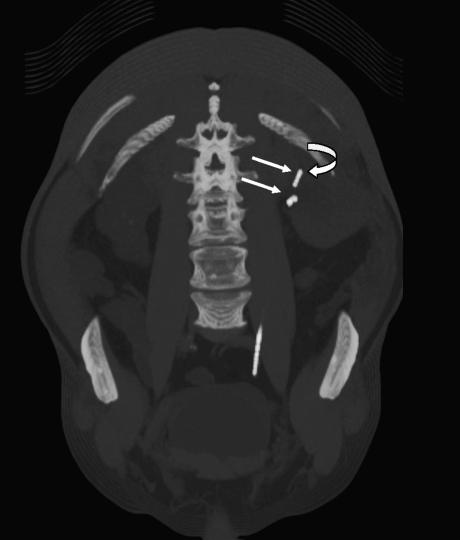

Urinary tract interventions can lead to multiple complications in the renal collecting system, including retained foreign bodies from endourologic or percutaneous procedures, such as stents, nephrostomy tubes, and others. We report a case of very delayed erosion of embolization coils migrating into the renal pelvis, acting as a nidus for stone formation, causing mild obstruction and finally leading to gross hematuria roughly 18 years post transarterial embolization. History is significant for a remote unsuccessful endopyelotomy attempt that required an urgent embolization.